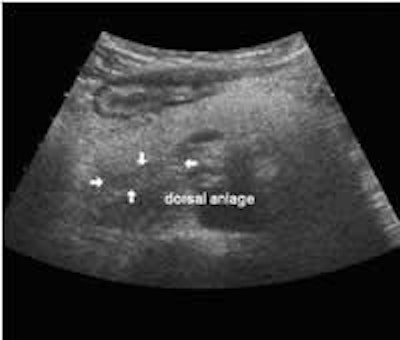

The following study describes anatomical landmarks in the ordinary pancreas of a thin patient:

Transverse planes in caudal direction:

Bright pancreas, clear dark dorsal bud (anlage):